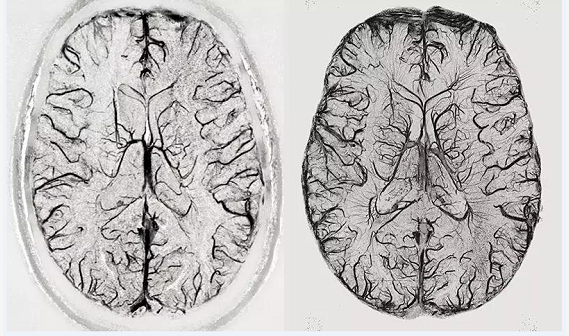

下面是德国马克斯普朗克研究所的9.4T(右)MRI和普通3T MRI扫描统一大脑断面的效果——

显然右边9.4T的机器扫出来细节丰满得多。